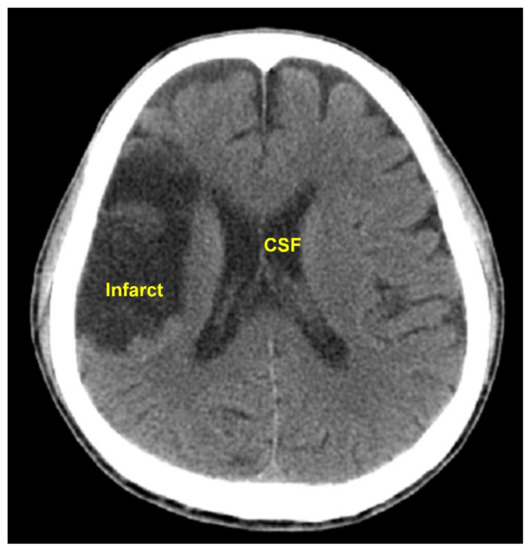

The pixel intensity transformation carried out in Step C4, Step C7, and Step P4 changed the HU of every pixel. It was an important image preprocessing function. The performance of our method would not have been satisfactory without this effort. The approximate HUs of air and bone are −1000 and 1000, respectively. The pixels in the intracranial tissues have HUs near 0. For example, the HU of CSF = 0, white matter = 25, gray matter = 35, and blood = 60 [14]. In Steps C4, C7, and P4, the distance between two consecutive HUs in the range −99 to 100 was enlarged by 11 times. Thus, the contrast of different tissues in the brain were enhanced. On the other hand, the HUs from −1000 to −100 and from 101 to 1000 only received a constant raise without a contrast enhancement. Another effort of the image preprocessing that contributed to the high accuracy rate was the elimination of the CSF, carried out in Step C8 and P5. CSF could have intensities close to those of the cerebral infarcts and might lead to false positive results. For instance, in the CT image shown in Figure 6, the intensity in the CST was close to that in the infarct region. The CST would be falsely detected as infarcted if it was not eliminated.

Figure 6. This CT image shows similar intensities of the CST and the infarct region. The CST could be falsely detected as infarcted if not eliminated before the infarct detection.